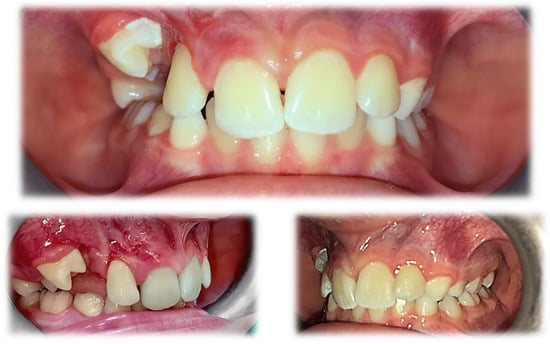

A functional assessment of the masticatory system did not reveal any kinematic jaw alteration. The movements of the mandible were symmetric, and their range was normal. Intraorally, mixed dentition was present with increased overjet and bilateral ½ cusp angle class II malocclusion. The oral vestibulum, in the area of the upper right primary canine (53) and first molar (54), was deformed due to alveolar bone expansion, and the overlying mucosa was red and swollen (Figure 2). The patient was referred for a radiological examination, as well as for a consultation at the Department of Oral Surgery.

Figure 2.

Intraoral photographs before treatment.